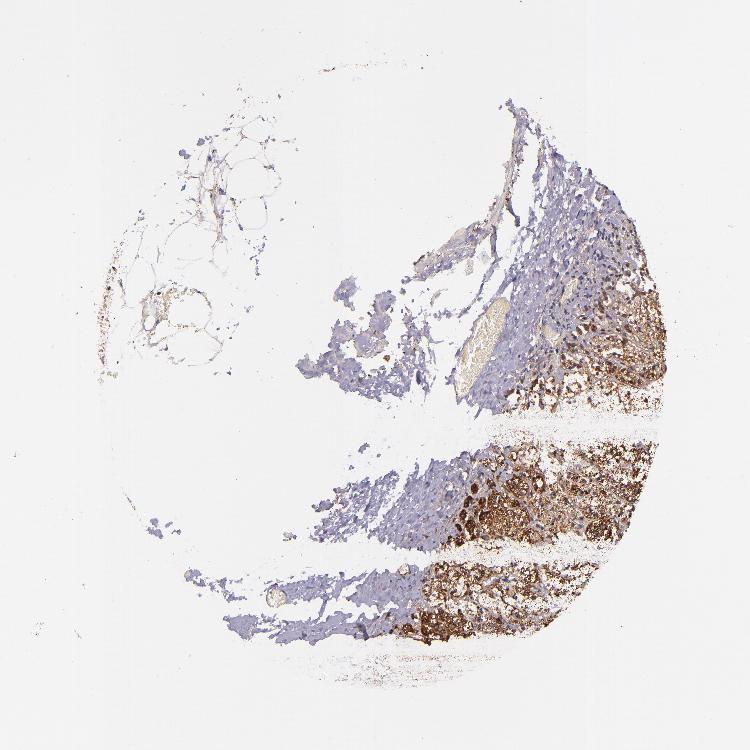

ADRENAL GLAND - Antibody stainingi

Antibody staining in the annotated cell types in the current human tissue is reported as not detected, low, medium, or high, based on conventional immunohistochemistry profiling in selected tissues. This score is based on the combination of the staining intensity and fraction of stained cells.

Each image is clickable and will lead to virtual microscopy that enables deeper exploration of all samples and also displays staining intensity scores, fraction scores and subcellular localization as well as patient and tissue information for each sample.

Antibody HPA000425Antibody HPA002017

Glandular cells MediumHigh